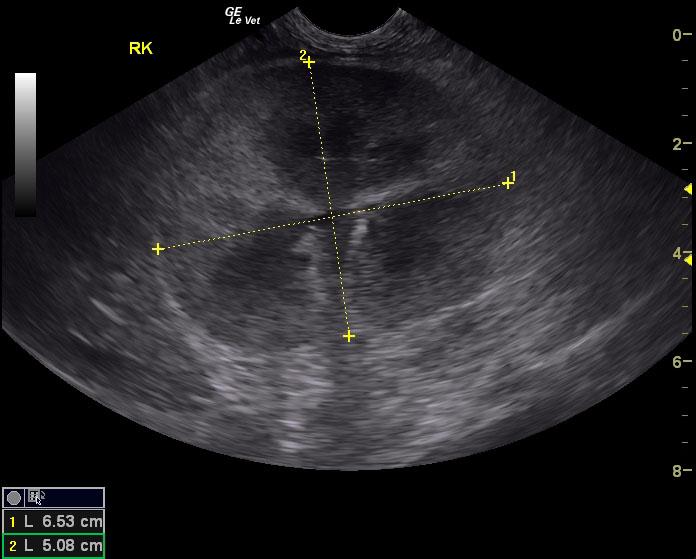

A 12½-year-old neutered male DSH cat with a history of hypertension controlled with amlodipine was presented for evaluation of PU/PD and weight loss. On physical examination, a cranial abdominal mass (suspected kidney) and moderate muscle atrophy was present. Abnormalities on CBC and serum biochemistry included neutrophilia and azotemia. Prior urine analysis had shown proteinuria with a SG of 1.028.

A 12½-year-old neutered male DSH cat with a history of hypertension controlled with amlodipine was presented for evaluation of PU/PD and weight loss. On physical examination, a cranial abdominal mass (suspected kidney) and moderate muscle atrophy was present. Abnormalities on CBC and serum biochemistry included neutrophilia and azotemia. Prior urine analysis had shown proteinuria with a SG of 1.028.